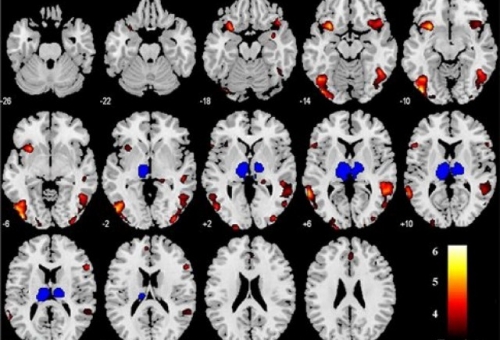

Εγκεφαλική περιοχή «προβλέπει» ό,τι κάτι κακό πρόκειται να συμβεί

Βρετανοί ερευνητές υποστηρίζουν ότι ανακάλυψαν μια περιοχή του εγκεφάλου, που «πυροδοτεί» το ενστικτώδες αίσθημα στον άνθρωπο ό,τι κάτι κακό πρόκειται...